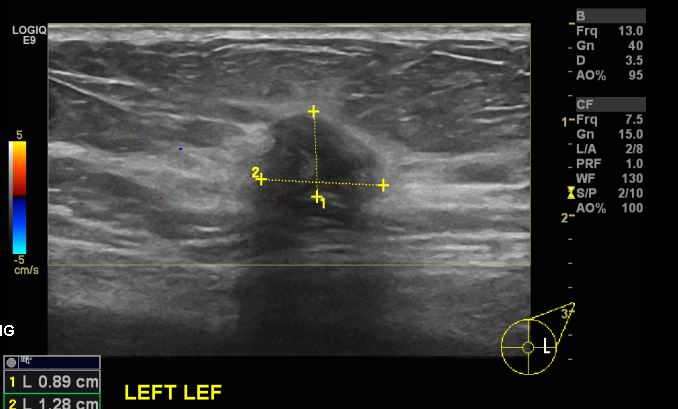

10일전쯤 우연히 왼쪽유방에 멍우리발견하여 내원하신 60대 환자분으로

본원에서 왼쪽상외측조직검사시행하신 후 침윤성유관암 진단되셨습니다.